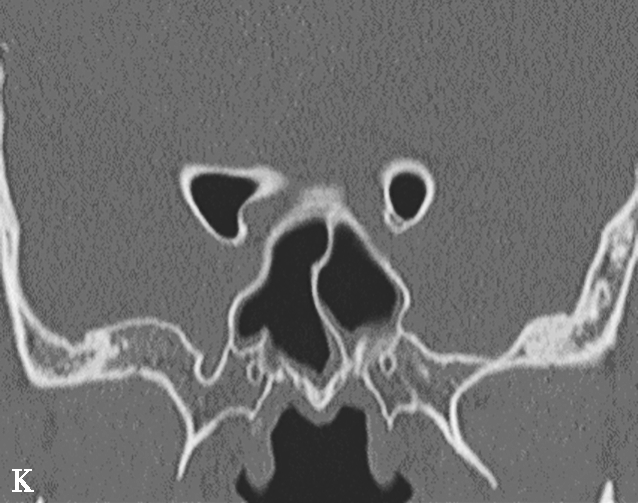

图1-3-7 蝶窦及蝶窦区解剖变异

A.颈内动脉管突入蝶窦;B.蝶窦间隔(白箭);C.左侧翼突气化;D.蝶嵴(星)、蝶骨大翼(白箭)、鞍背气化(虚箭);E.蝶骨小翼气化(白箭);F、G.鞍前型蝶窦(三角);H、I.甲介型蝶窦;J、K.鞍型蝶窦;L.Odoni气房(白箭)